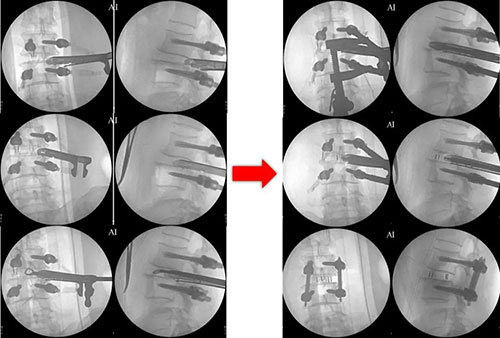

在助手副主任医师李涛、张稳博士辅助下,蒋振松主任医师成功为患者实施椎间孔镜下腰椎融合手术,这也是山东省立医院首例椎间孔镜下腰椎融合手术。手术出血量约50ml,不用放置引流管。患者术后腰痛及下肢疼痛、麻木症状完全缓解,复查X光片显示滑脱完全复位,内固定物位置良好。复查CT和MRI显示侧隐窝狭窄解除,恢复正常椎管容积。患者术后3天CRP、血沉即恢复正常,佩戴腰围下地活动,随即出院。患者及家属对手术效果非常满意。

术后MRI、CT

术后X光